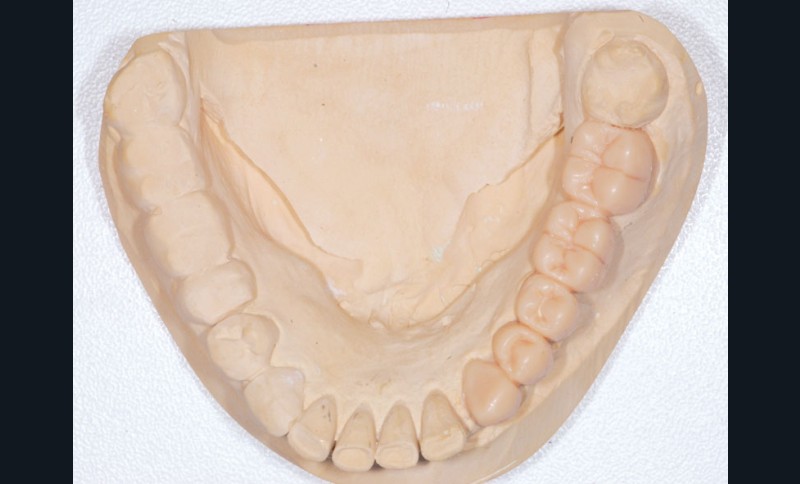

Le modèle de travail est fabriqué au laboratoire, des piliers CFAO Atlantis™ sont réalisés en fonction du bridge antagoniste transitoire.